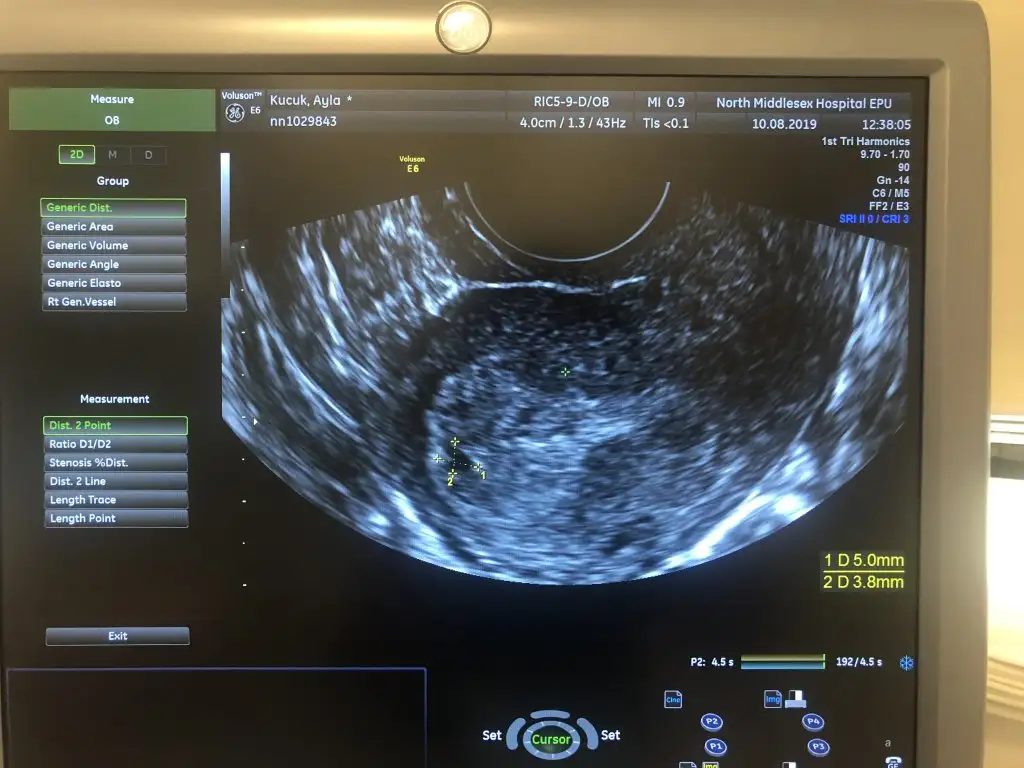

Bu hafta sali 1970 ctesi(bugun) 3200du. Doktor gecen haftadan beri iki uc gun arayla alttan ultrasonla bakiyordu goremiyordu. En son cuma gunu kucucuk bi kararti gormustu rahim icinde ama kese oldugundan emin olmamisti. Sali gunu biraz buyumustu bugunde cok azcik buyumustu o gordugu yapi. 5.8 *3 mm dedi. Onun hala kese oldugundan emin degil ve 3200le kesinlikle alttan net gorunmesi gerekiyodu dedi. Pteside goremezse dis gebelik teshisi kesinlesecek dis gebelik yasayan arkadaslar tecrubelerinizi yazabilirmisiniz?